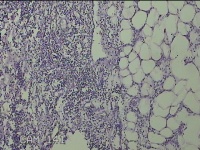

性别

男

年龄

56岁

临床诊断

右侧腋下结节

一般病史

标本名称

大体所见

灰白粉红色组织2.3x2x0.8cm一块,表面带梭形皮肤2.3x2cm,皮下见结节2x1cm一个,结节部分已切开,见结节呈囊性,囊内有少许灰白色角化物,囊壁厚0.1cm。

炎性病变。